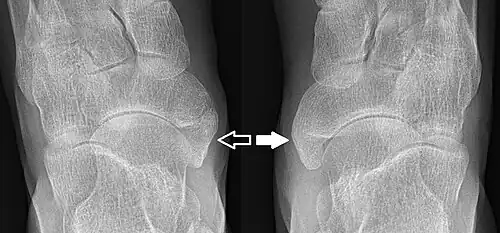

Type 2 on one foot (dark arrow) and type 3 on the other (white arrow)